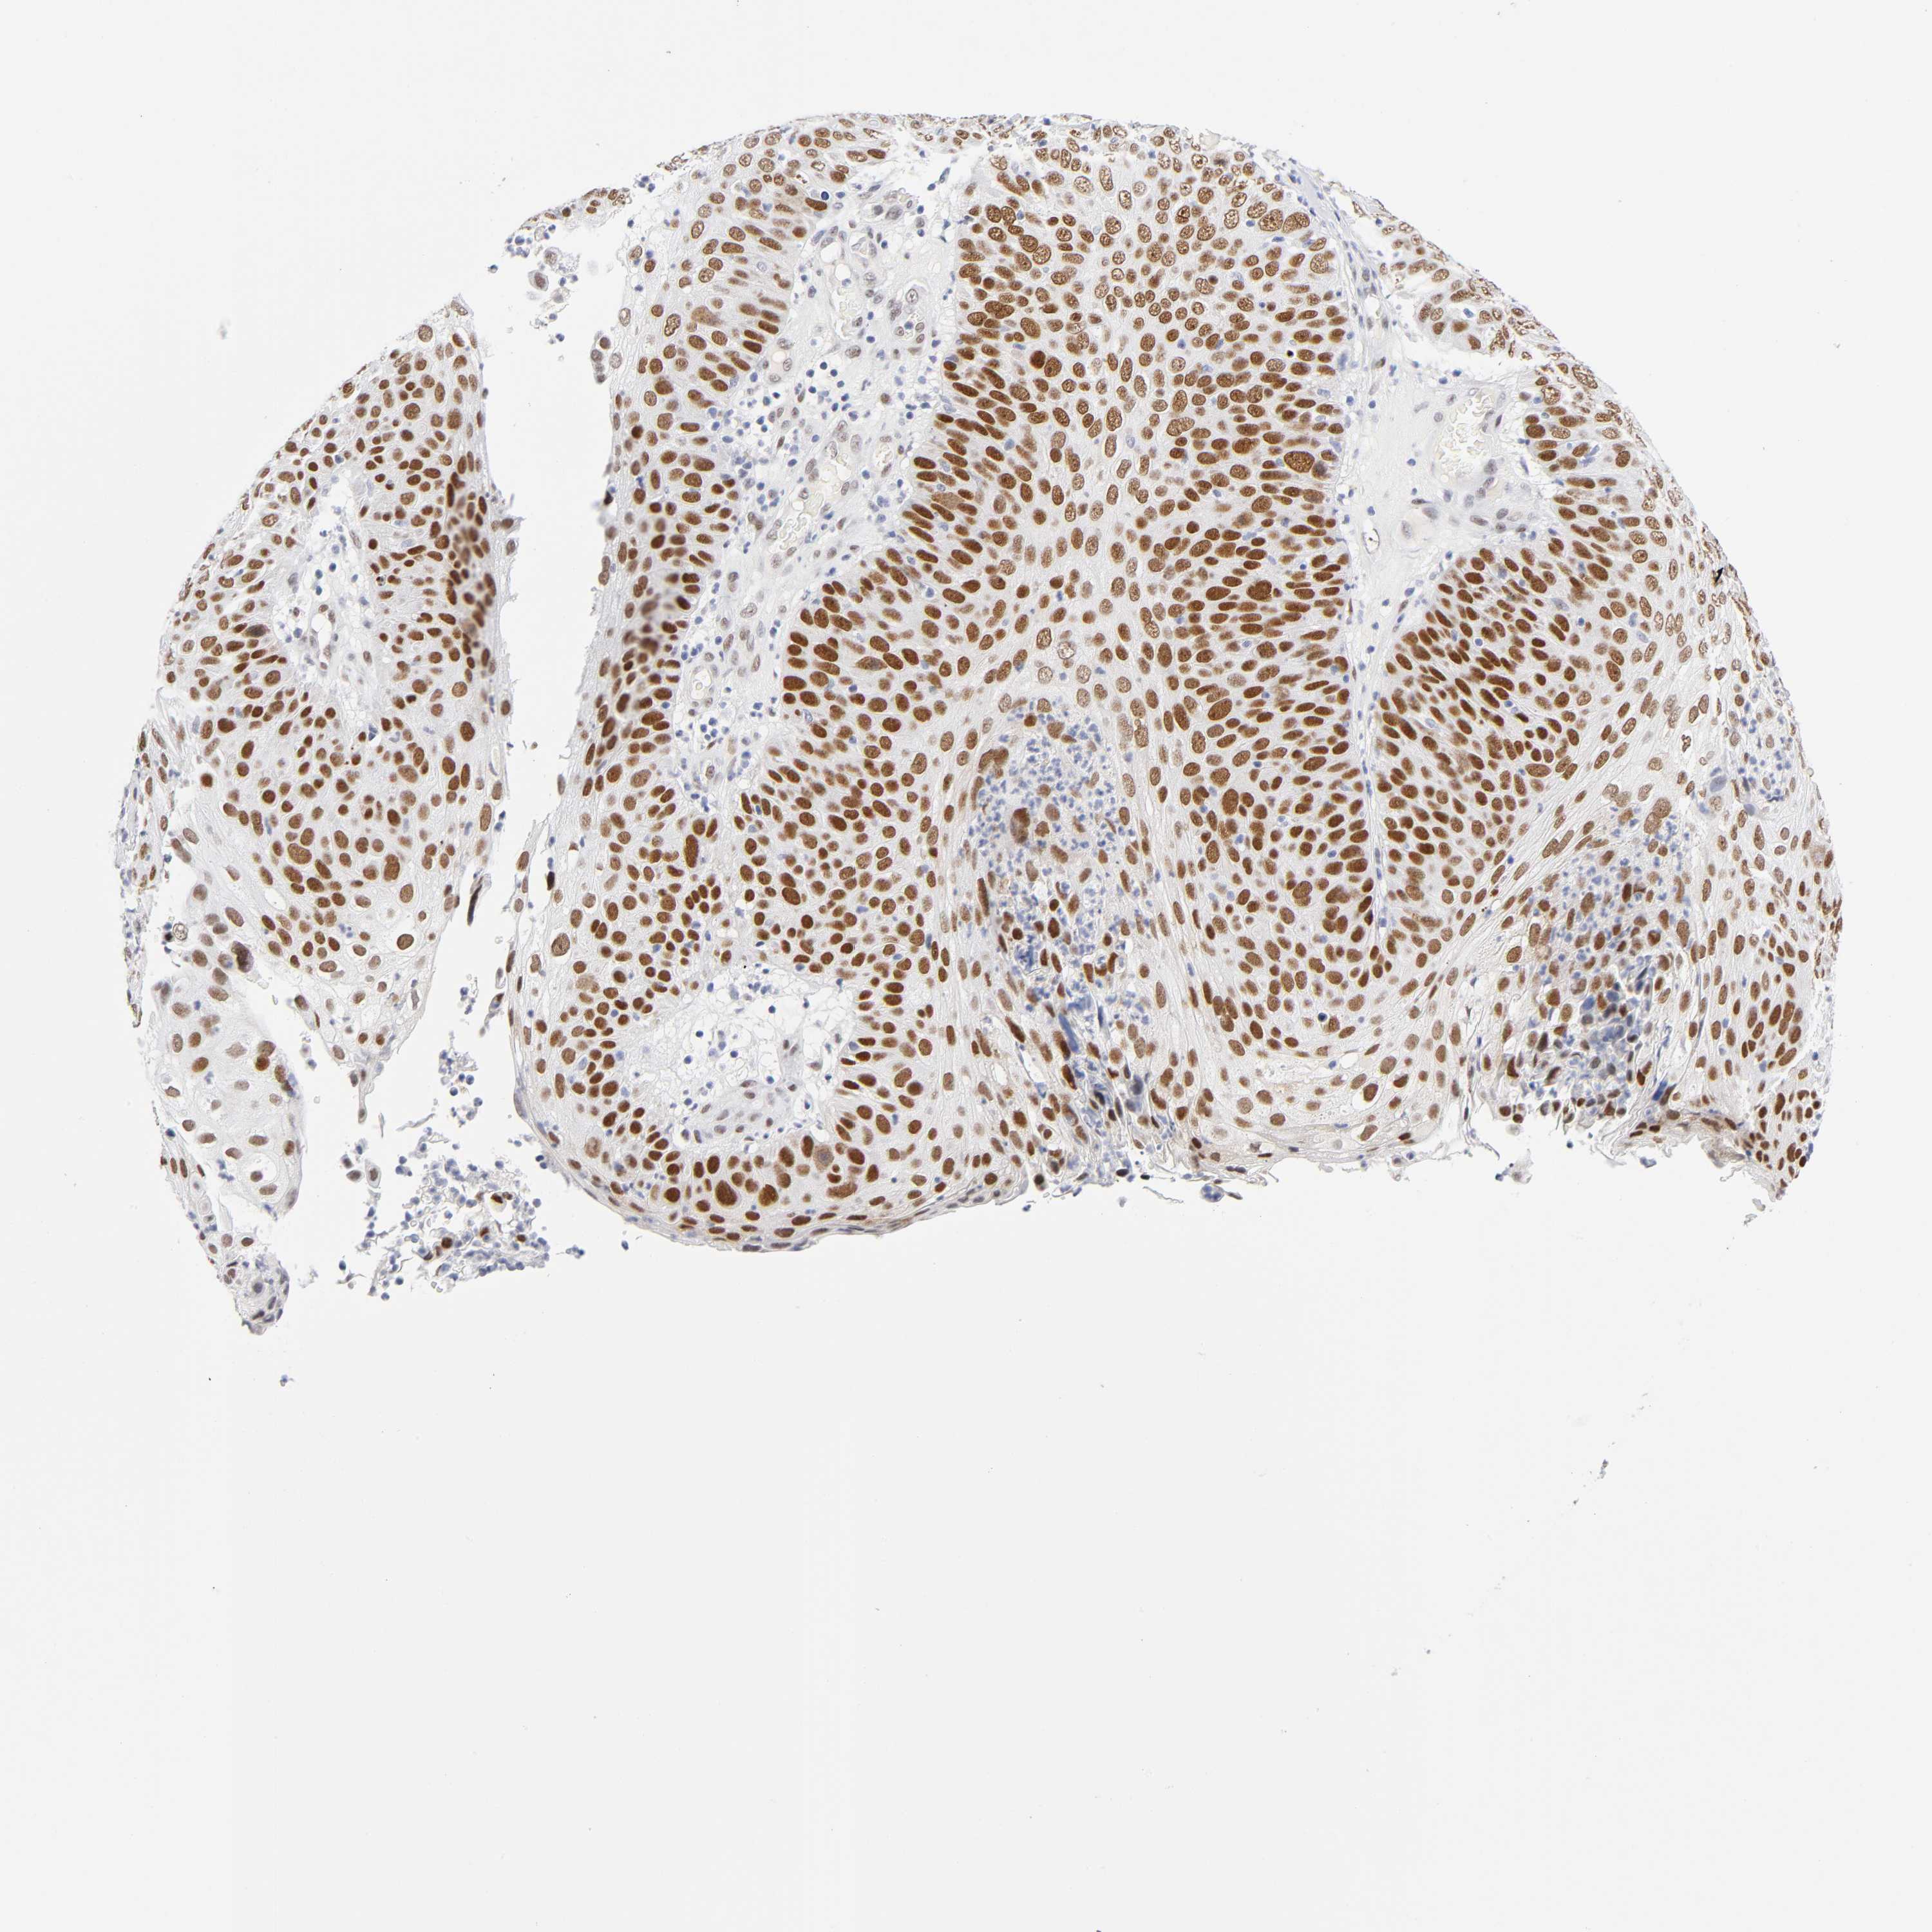

SKIN CANCER - Protein expressioni

A mouse-over function shows sample information and annotation data. Click on an image to view it in a full screen mode. Samples can be filtered based on level of antibody staining by selecting one or several of the following categories: high, medium, low and not detected. The assay and annotation is described here.

Antibody stainingi

Antibody staining in the annotated cell types in the current human tissue is reported as not detected, low, medium, or high, based on conventional immunohistochemistry profiling in selected tissues. This score is based on the combination of the staining intensity and fraction of stained cells.

Each image is clickable and will lead to virtual microscopy that enables deeper exploration of all samples and also displays staining intensity scores, fraction scores and subcellular localization as well as patient and tissue information for each sample.

Antibody CAB004674

Squamous cell carcinoma, NOS